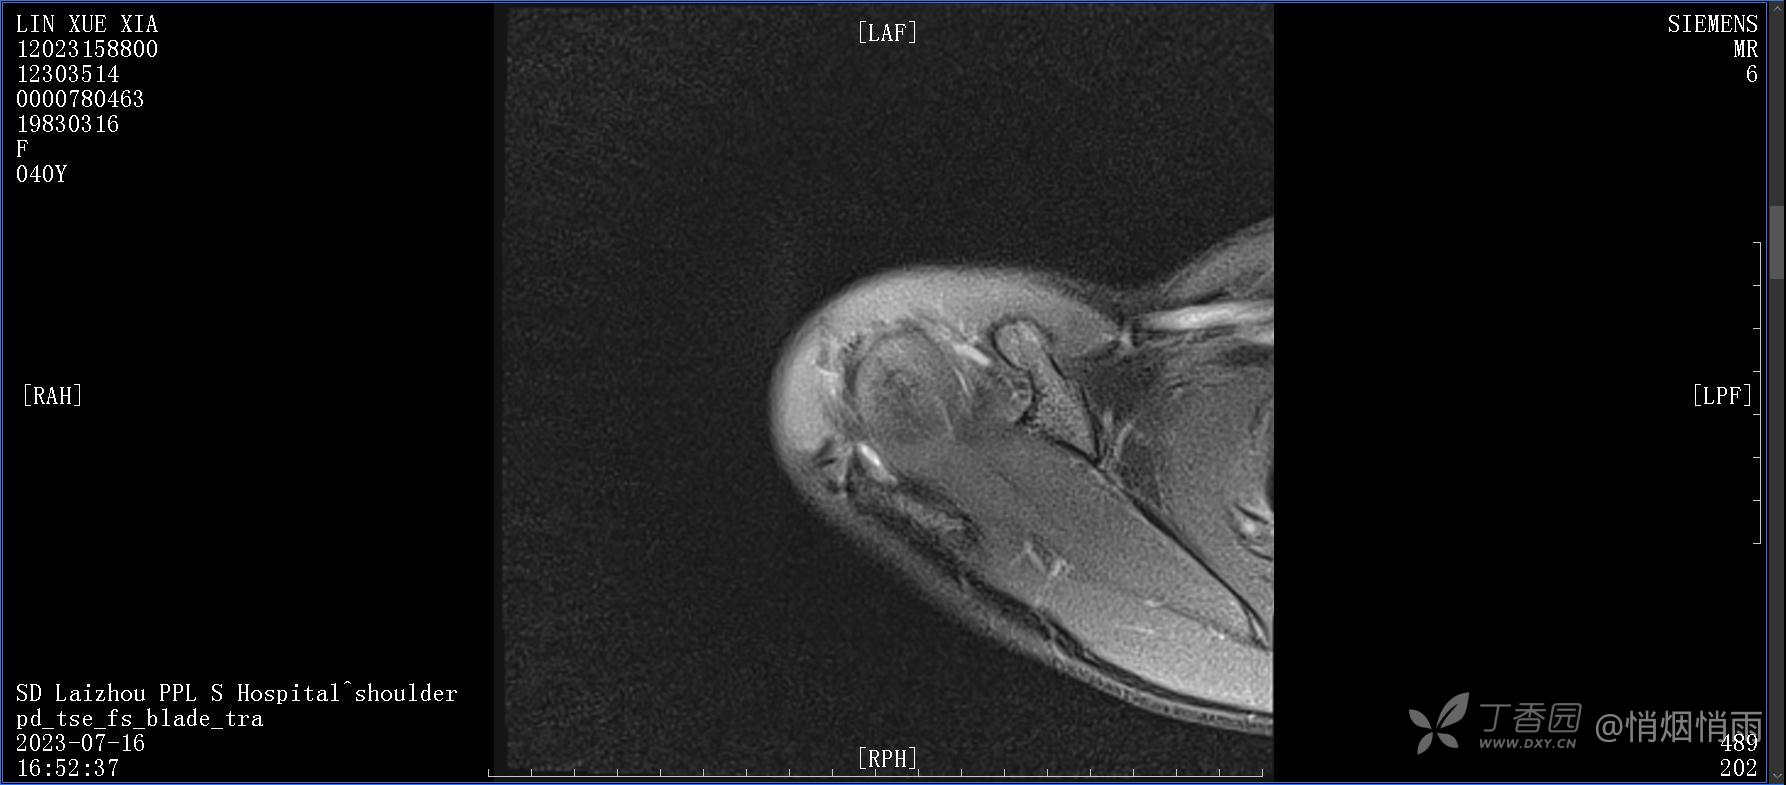

查体:右肩关节局部轻度肿胀,肩胛区压痛明显,痛处不固定,肩关节痛性活动受限,jobe test(+),lift -off test(+),中指、环指感觉较余指减退,余肢端感觉及血运情况可。

目前的诊断,暂时依据辅助检查诊为肩袖损伤,但是患者疼痛的性质和特点,却不是单纯的肩袖损伤所致。考虑过胸廓出口综合征,但是该疾病会出现肩胛区的疼痛吗?(由于考虑到费用的问题,没再进行下一步的检查)带状疱疹会有如此的症状吗?